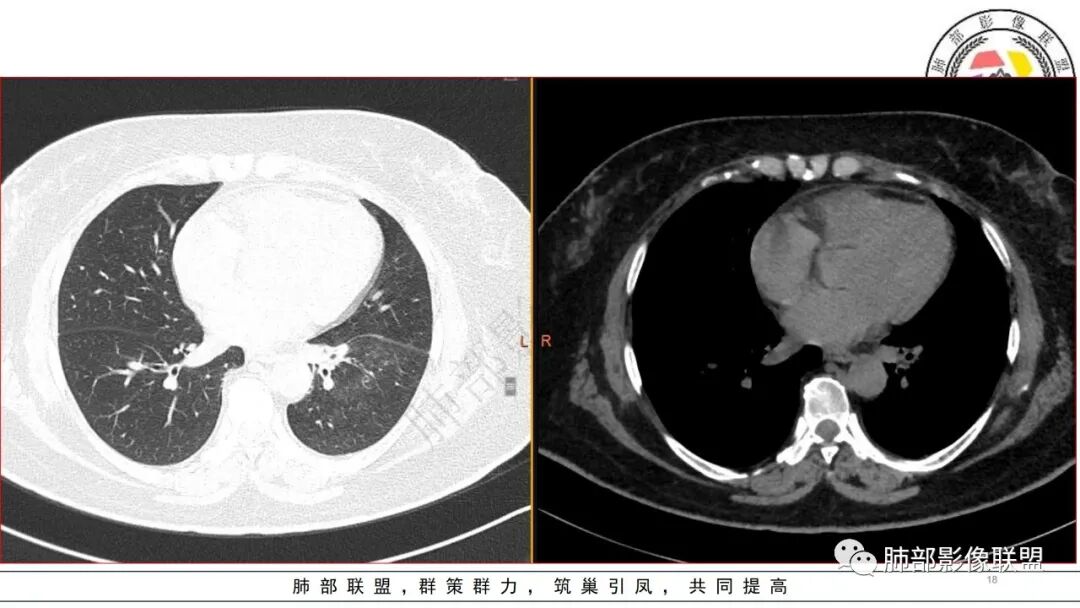

老年女性,有14年糖尿病史,咳嗽、喘息2天。白细胞计数稍升高。1.13CT:左下肺大片实变,经抗感染治疗,短期变为多发气囊及空洞样病灶。病灶考虑气道来源,短期变化大,不支持肺结核诊断;无咯血症状,短时间内变化大,毛霉可能性小;肺克及金葡感染难以鉴别,建议完善降钙素原检查进一步判断。个人倾向于肺克。

短期内变化明显,左下肺随治疗进展可见气囊影,实变内可见空洞及支扩,考虑炎性感染性病变,病史较短,变化较大,可排除丅B及奴卡,无咳血可排除毛霉,综和考虑金葡>肺克,其次要考虑合并铜绿感染的可能

1.局限于单肺叶的大范围实性密度影,边界不清,看不出外壁的液化空洞,多符合化脓性感染。

2.数天内变化明显,肿瘤性病变,结核、真菌、努卡等感染几乎不在鉴别诊断之列。

3.金黄色葡萄球菌临床中毒症状明显,常寒颤高热起病,血源性感染者常有皮肤脓肿、伤口感染、蜂窝织炎、化脓性骨髓炎等等。病情变化快,影像进展迅速,短期内(如一两天内)迅速出现的有张力的菲薄气囊影,或多发成串分布的,尤具特征性!较之其他感染,短期内易出现脓胸。本例上述特征似乎不明显。